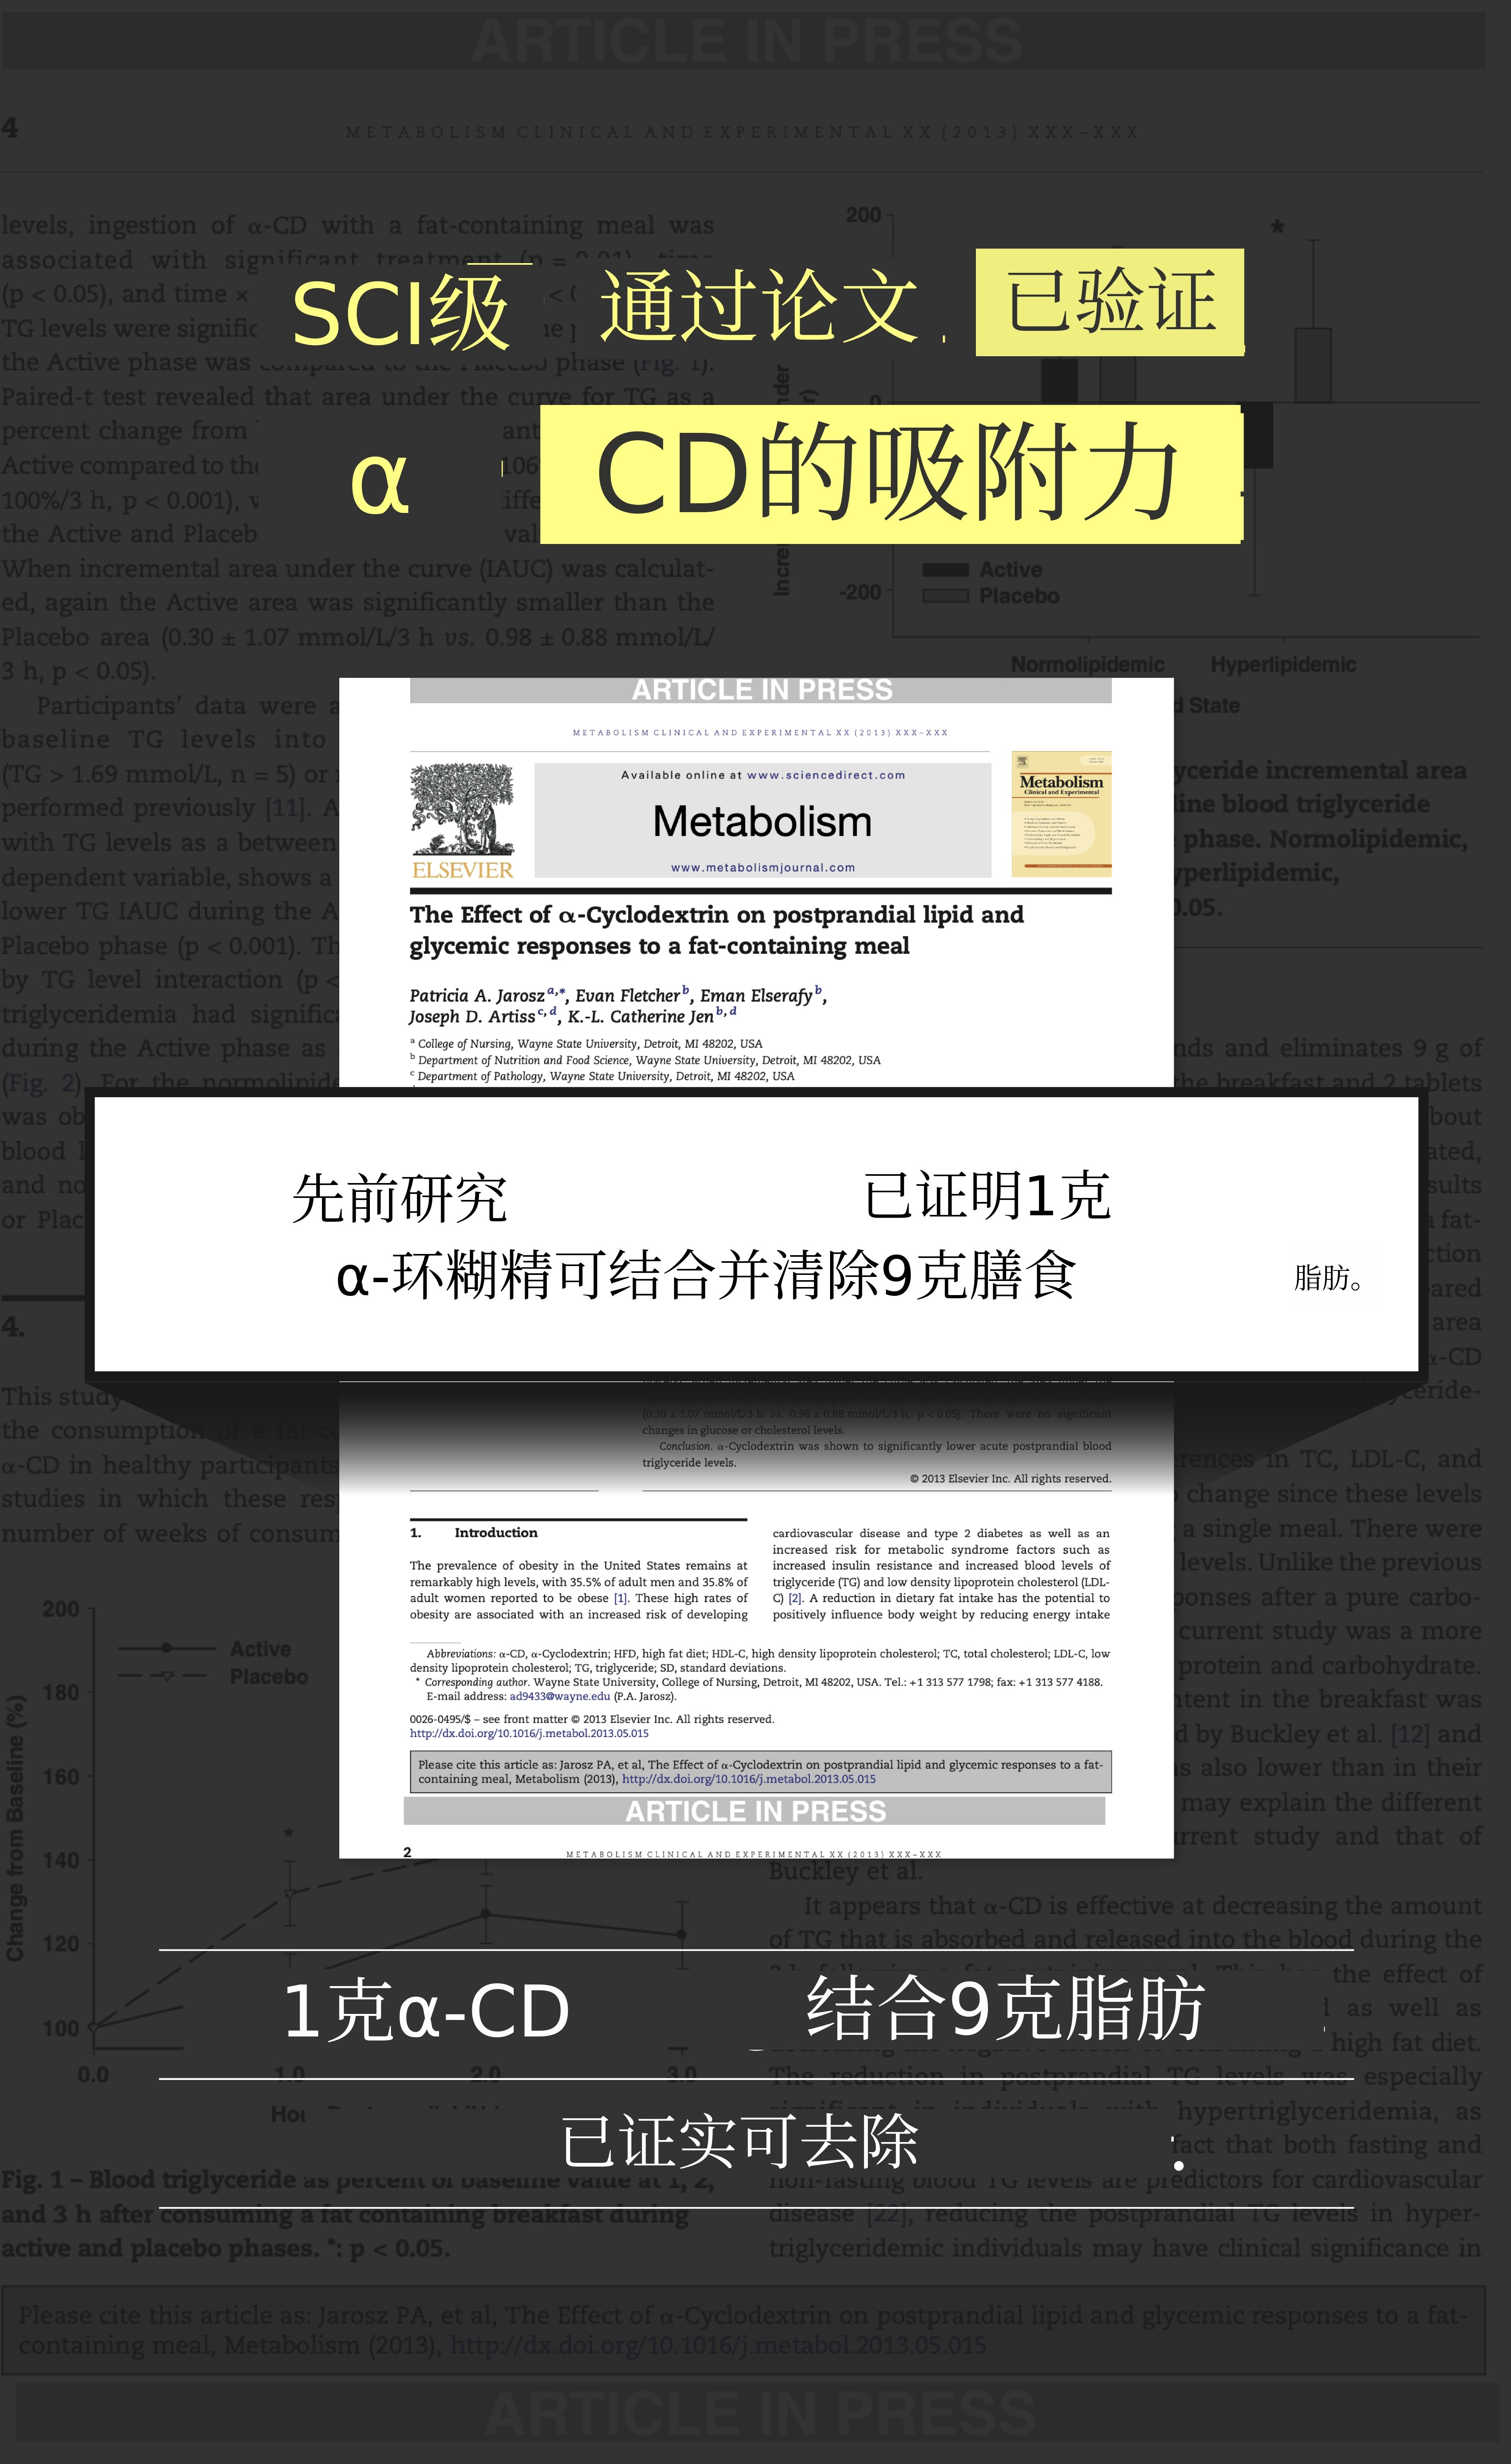

我阅读了100多篇论文,最终找到了“仙人掌”和“α-环状糊精”。但找到成分并不是结束。我逐一确认是否真的有效,是否有科学验证。每次见到熟人时都会分给他们试用,听取反馈。“平时肯定会胖1公斤,反而瘦了”,“确实感觉轻盈了”等反馈不断,让我确信只有这个组合才行。